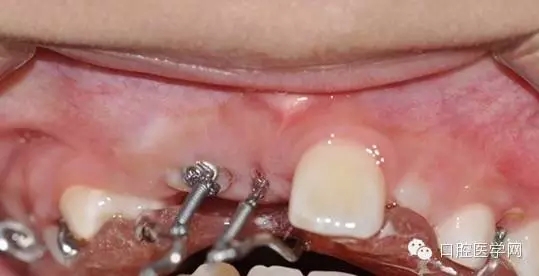

縫合后,要把鏈子留到外邊:

32.webp.jpg

一周后拆線 :

33.webp.jpg